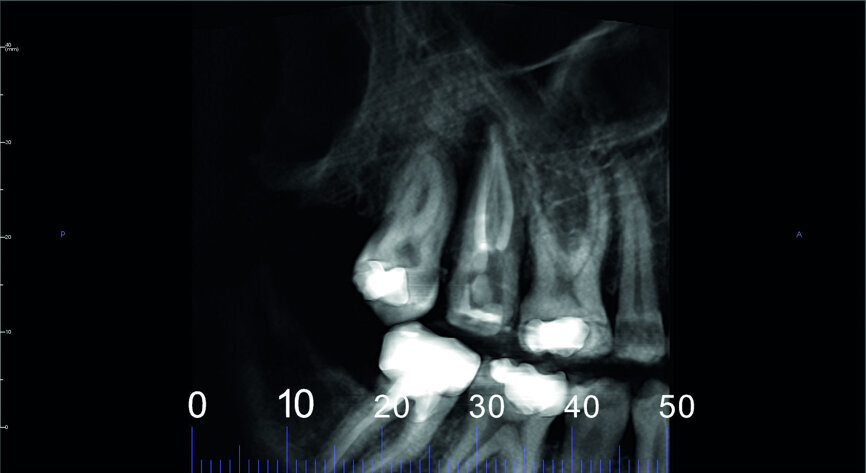

Fig. 4: Pre-op CBCT scan, pseudo-panoramic view.

A 47-year-old male patient in a good medical condition and a non-smoker was referred to our dental practice for endodontic retreatment of the right maxillary second molar. The dental history revealed that the tooth had been endodontically treated three months before because of acute pulpitis. After the treatment, the patient complained of pain on chewing. Antibiotics and a non-steroidal anti-inflammatory drug were prescribed, but the pain remained. After a month, a sinus tract appeared. The tooth was retreated in another practice without success. The clinical inspection revealed the presence of a sinus tract near the apical region of tooth #17. The tooth had been prepared for a full crown, but was without even a temporary crown, and the access cavity had been closed with temporary filling material. Cracks were evident on the buccal and mesial surfaces. Periodontal probing showed a deep pocket (> 12 mm) on the distal aspect of the root trunk (Figs. 1 & 2). The periapical radiograph showed a radiolucency between the roots of the second and third molars. The radiographic appearance of the endodontic treatment was good, without clear evidence of periapical radiolucencies (Fig. 3). A perforation of the pulp chamber floor was suspected. A CBCT scan was performed (Figs. 4–7), and it confirmed the suspicion of perforation, along with the presence of a large periradicular radiolucency and an unfavourable root shape.